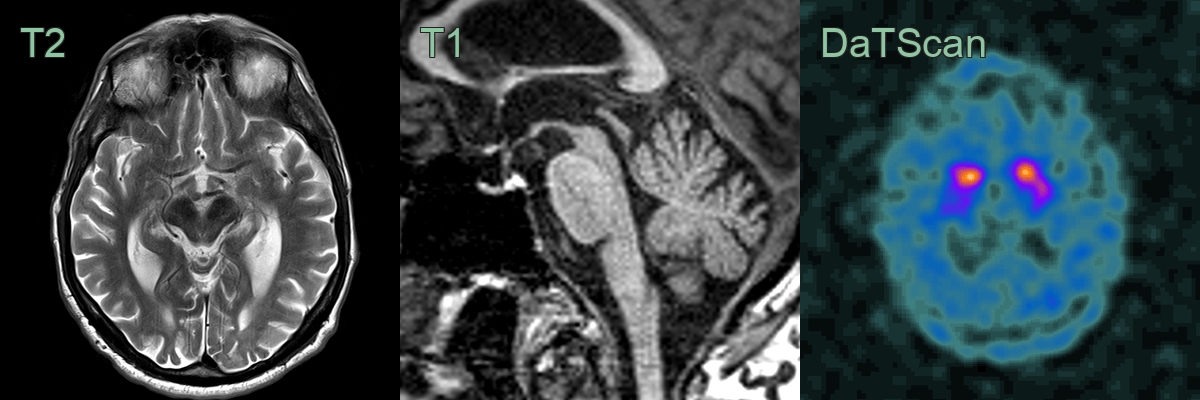

• 65-year-old patient presented with instability, free falls, and a vertigcal gaze palsy.

• MRI showed marked atrophy of the pons.

• DaTscan showed loss of normal tracer uptake in both corpora striata.